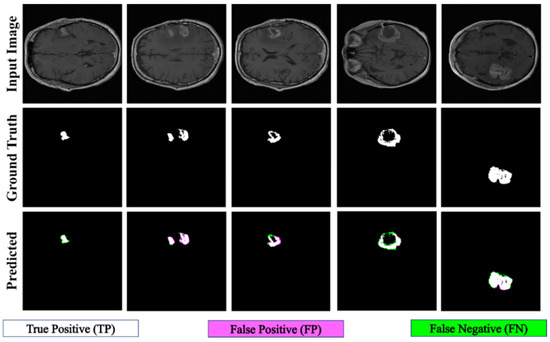

| Results | ET | TC | WT | Heterogeneous | ||||

|---|---|---|---|---|---|---|---|---|

| Figure 11a | Figure 11b | Figure 12a | Figure 12b | Figure 13a | Figure 13b | Figure 14a | Figure 14b | |

| FD | 1.1956 | 1.1312 | 1.2887 | 1.2562 | 1.5601 | 1.4406 | 1.0776 | 1.3711 |

| R2 | 0.957 | 0.934 | 0.983 | 0.96 | 0.982 | 0.98 | 0.983 | 0.954 |

| C | 0.9783 | 0.9665 | 0.9915 | 0.9799 | 0.9909 | 0.9901 | 0.9913 | 0.9768 |